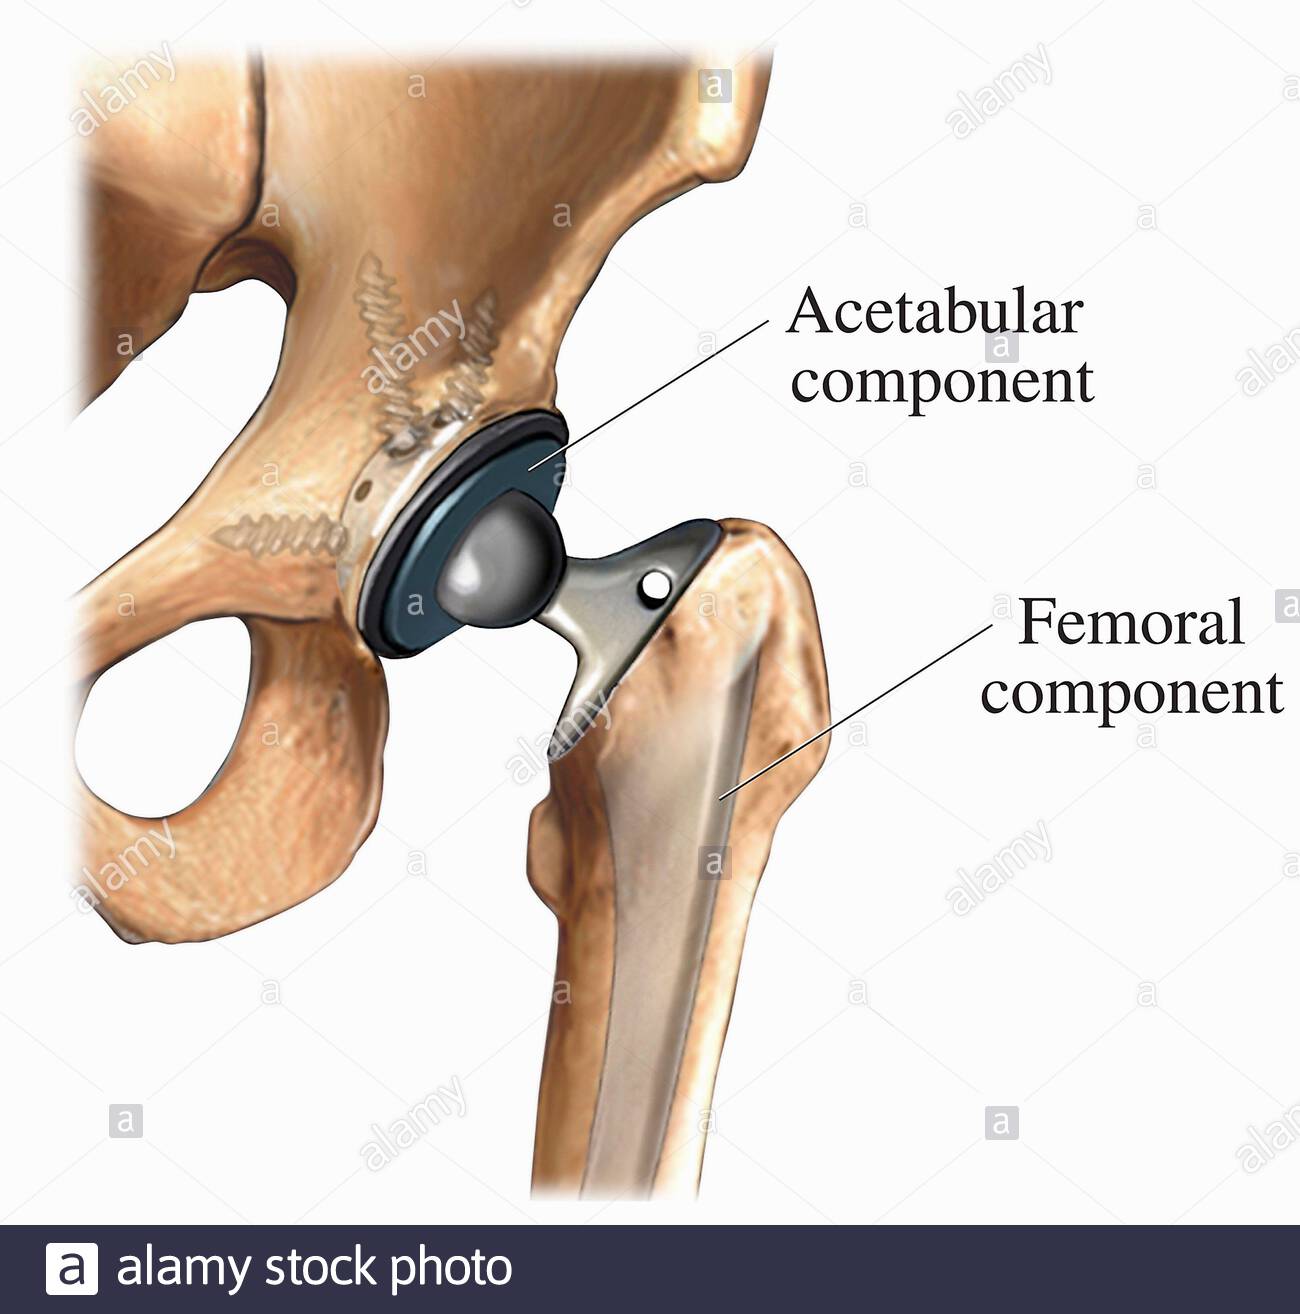

Замена таз сустава

Замена таз сустава 113 фотографий